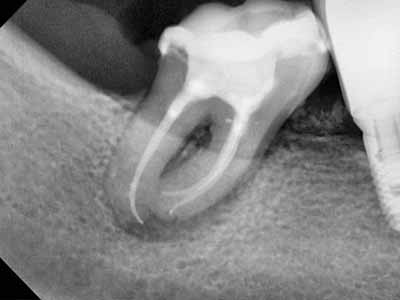

Frontier in Micro Dentistry and Endodontics

drg. Dennis,MDSc.,Sp.KG, Subsp. KE(K)., Ph.D

Dokter Gigi Spesialis Konservasi Gigi Konsultan, Master of Dental Science